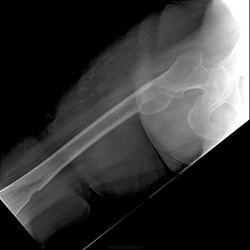

Апрельская МСКТ. "МСК-томография, толщина срезов 1-5мм, при анализе использована МР-реконструкция. Проекция: аксиальная. Контрастное усиление не проводилось. В верхней трети правой бедренной кости по медиальной поверхности наличие участка 4,6х1,9см с нарушением целостности наружной и внутренней костных пластинок. Видимой периостальной реакции не выявлено. Напротив дефекта костно-мозговой канал заполнен мягкотканным содержимым, которое распространяется также наружу. В нижней/3 правой бедренной кости дефект наружного компактного слоя на протяжении 1см. Мягкотканного компонента и венчика остеосклероза не выявлено. ЗАКЛЮЧЕНИЕ. По КТ больше данных за объёмное образование в/3, н/3 правой БК с наличием мягкотканного компонента. Рекомендована сцинтиграфия, биопсия.

ЗАКЛЮЧЕНИЕ: учитывая клинико-морфологические данные и выявленный иммунопрофиль, опухолевый узел (в зоне бедренной кости – клинически) с большой вероятностью является низкодифференцированной миогенной саркомой с признаками сосудистого происхождения –ЗЛОКАЧЕСТВЕННОЙ ГЛОМИЧЕСКОЙ ОПУХОЛЬЮ, хотя окончательно исключить злокачественную миоперицитому, миофибросаркому кости или крупноклеточную атипическую саркому Юинга не представляется возможным в связи с отсутствием рентгенологических данных."

Цитата полная, буквальная, выделение - моё. Исследование выполнено в областной клинической онкологической больнице. Представленные в начале ветки рентгенограммы выполнены после иммуногистохимии. Загашник-то... того: теперь пустой))).